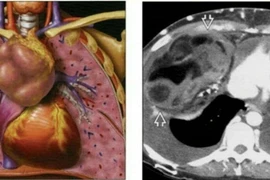

Đau vai gáy 6 năm nhưng chị Vũ Thị Th. (55 tuổi, ở Hưng Yên), nghĩ là do mình làm nghề thợ may, phải ngồi nhiều. Tuy nhiên, khi cơn đau tăng nặng và đi khám, bác sĩ chẩn đoán bệnh nhân bị u trung thất trước kích thước lớn xâm lấn tim và phổi.

(khoahocdoisong.vn) - Nhờ sự kết hợp nhiều chuyên khoa các bác sĩ Bệnh viện Bạch Mai đã cứu bệnh nhân có khối u trung thất lớn xâm lấn tim, phổi, làm tắc mạch...